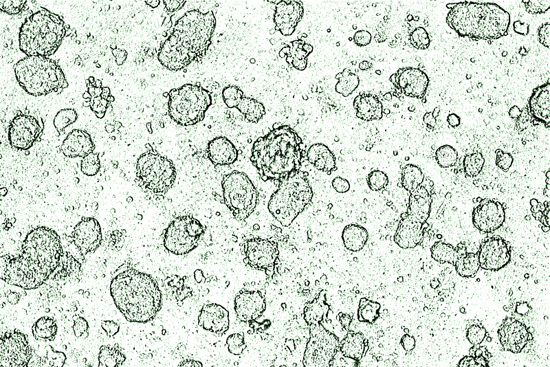

Developing a New Weapon Against HIV

Health & Medicine